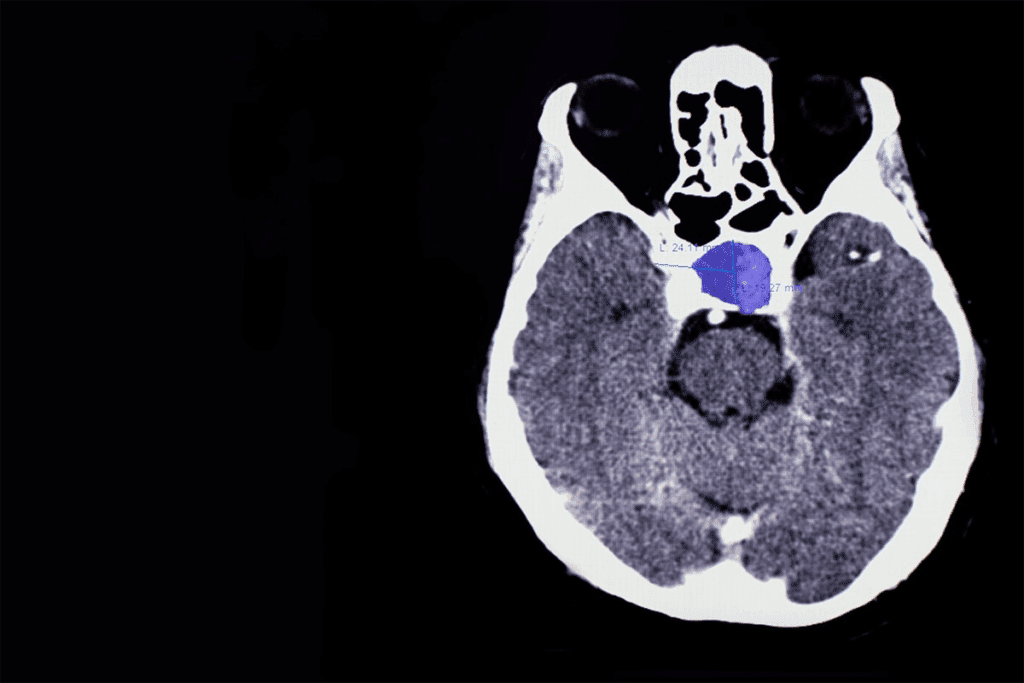

Pituitary Tumors and Their Effects

Pituitary tumors are growths that can mess with hormone levels. They can be functioning or non-functioning. Either way, they can cause headaches and vision problems.

Doctors use MRI scans and blood tests to diagnose these tumors. Treatment might include surgery, radiation, or medicines to manage hormone levels.